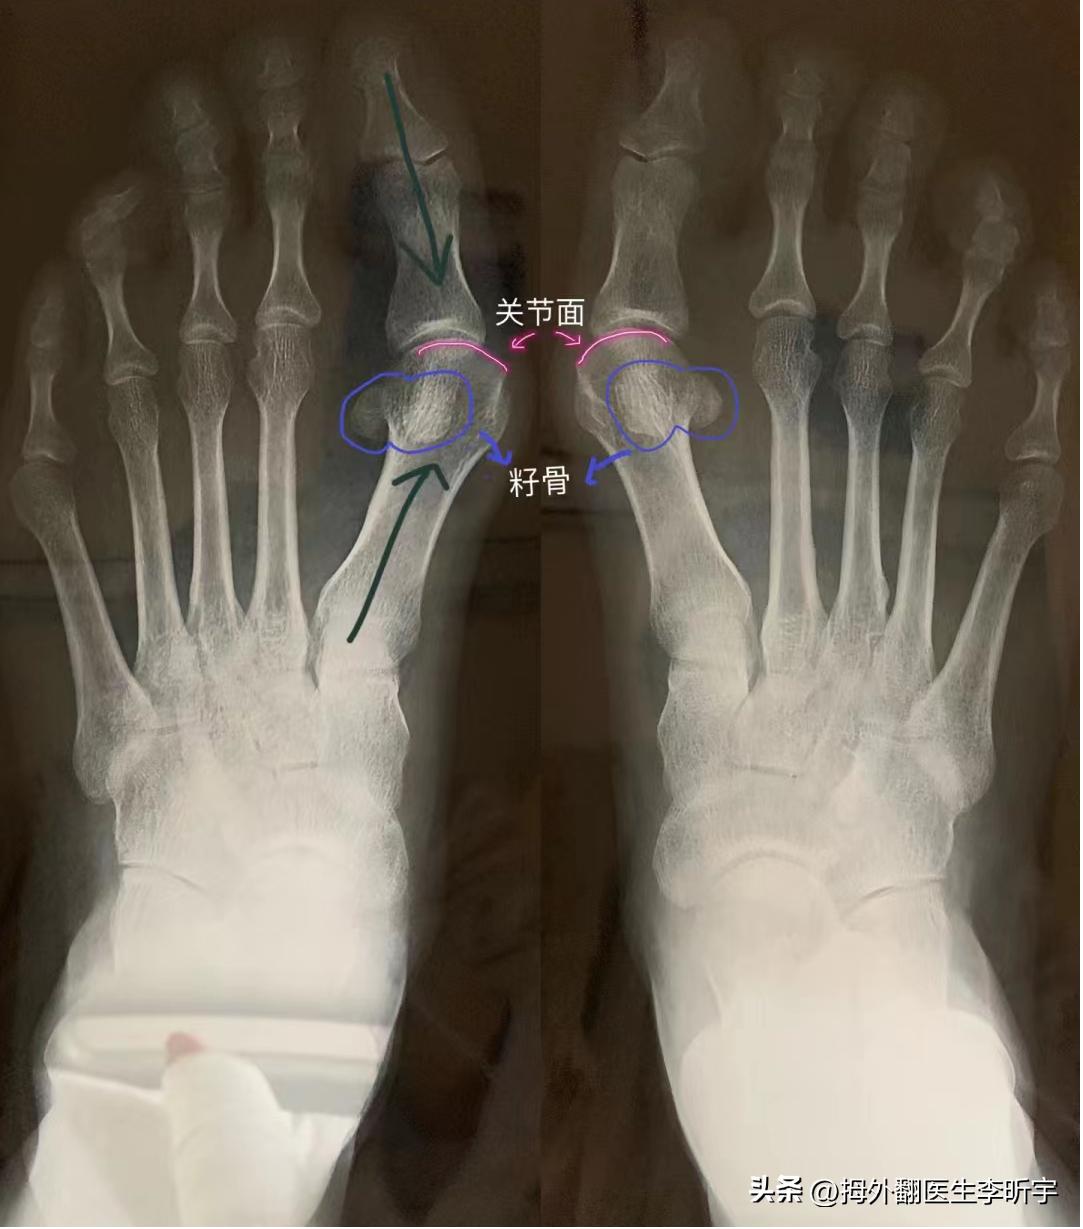

这里附上一张脚部骨头的解剖图,第一跖骨比二三四五跖骨都要粗,是因为第一跖骨出厂时候被设计的就是要承担主要的负重的,跖骨下面还有籽骨(圈出来的位置)。

有了拇外翻后,因为第一跖骨偏移了,力线就歪了,那么就会增加第二跖骨的受力,第二跖骨承担了它出厂时不该承受的重量,所以二三趾下面就会有茧子,咯脚。茧子越厚,说明足横弓塌陷越严重。